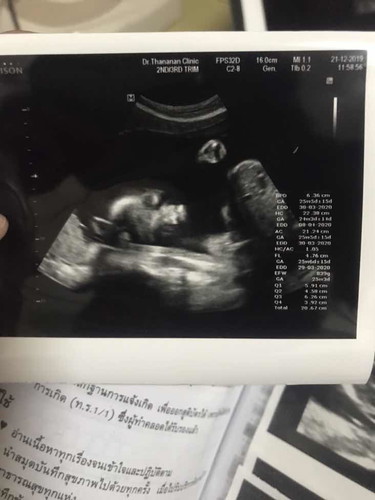

น้ำหนักทารกในครรภ์

อายุครรภ์25วีค น้องน้ำหนัก839กรัม น้อยไปรึป่าวคะ